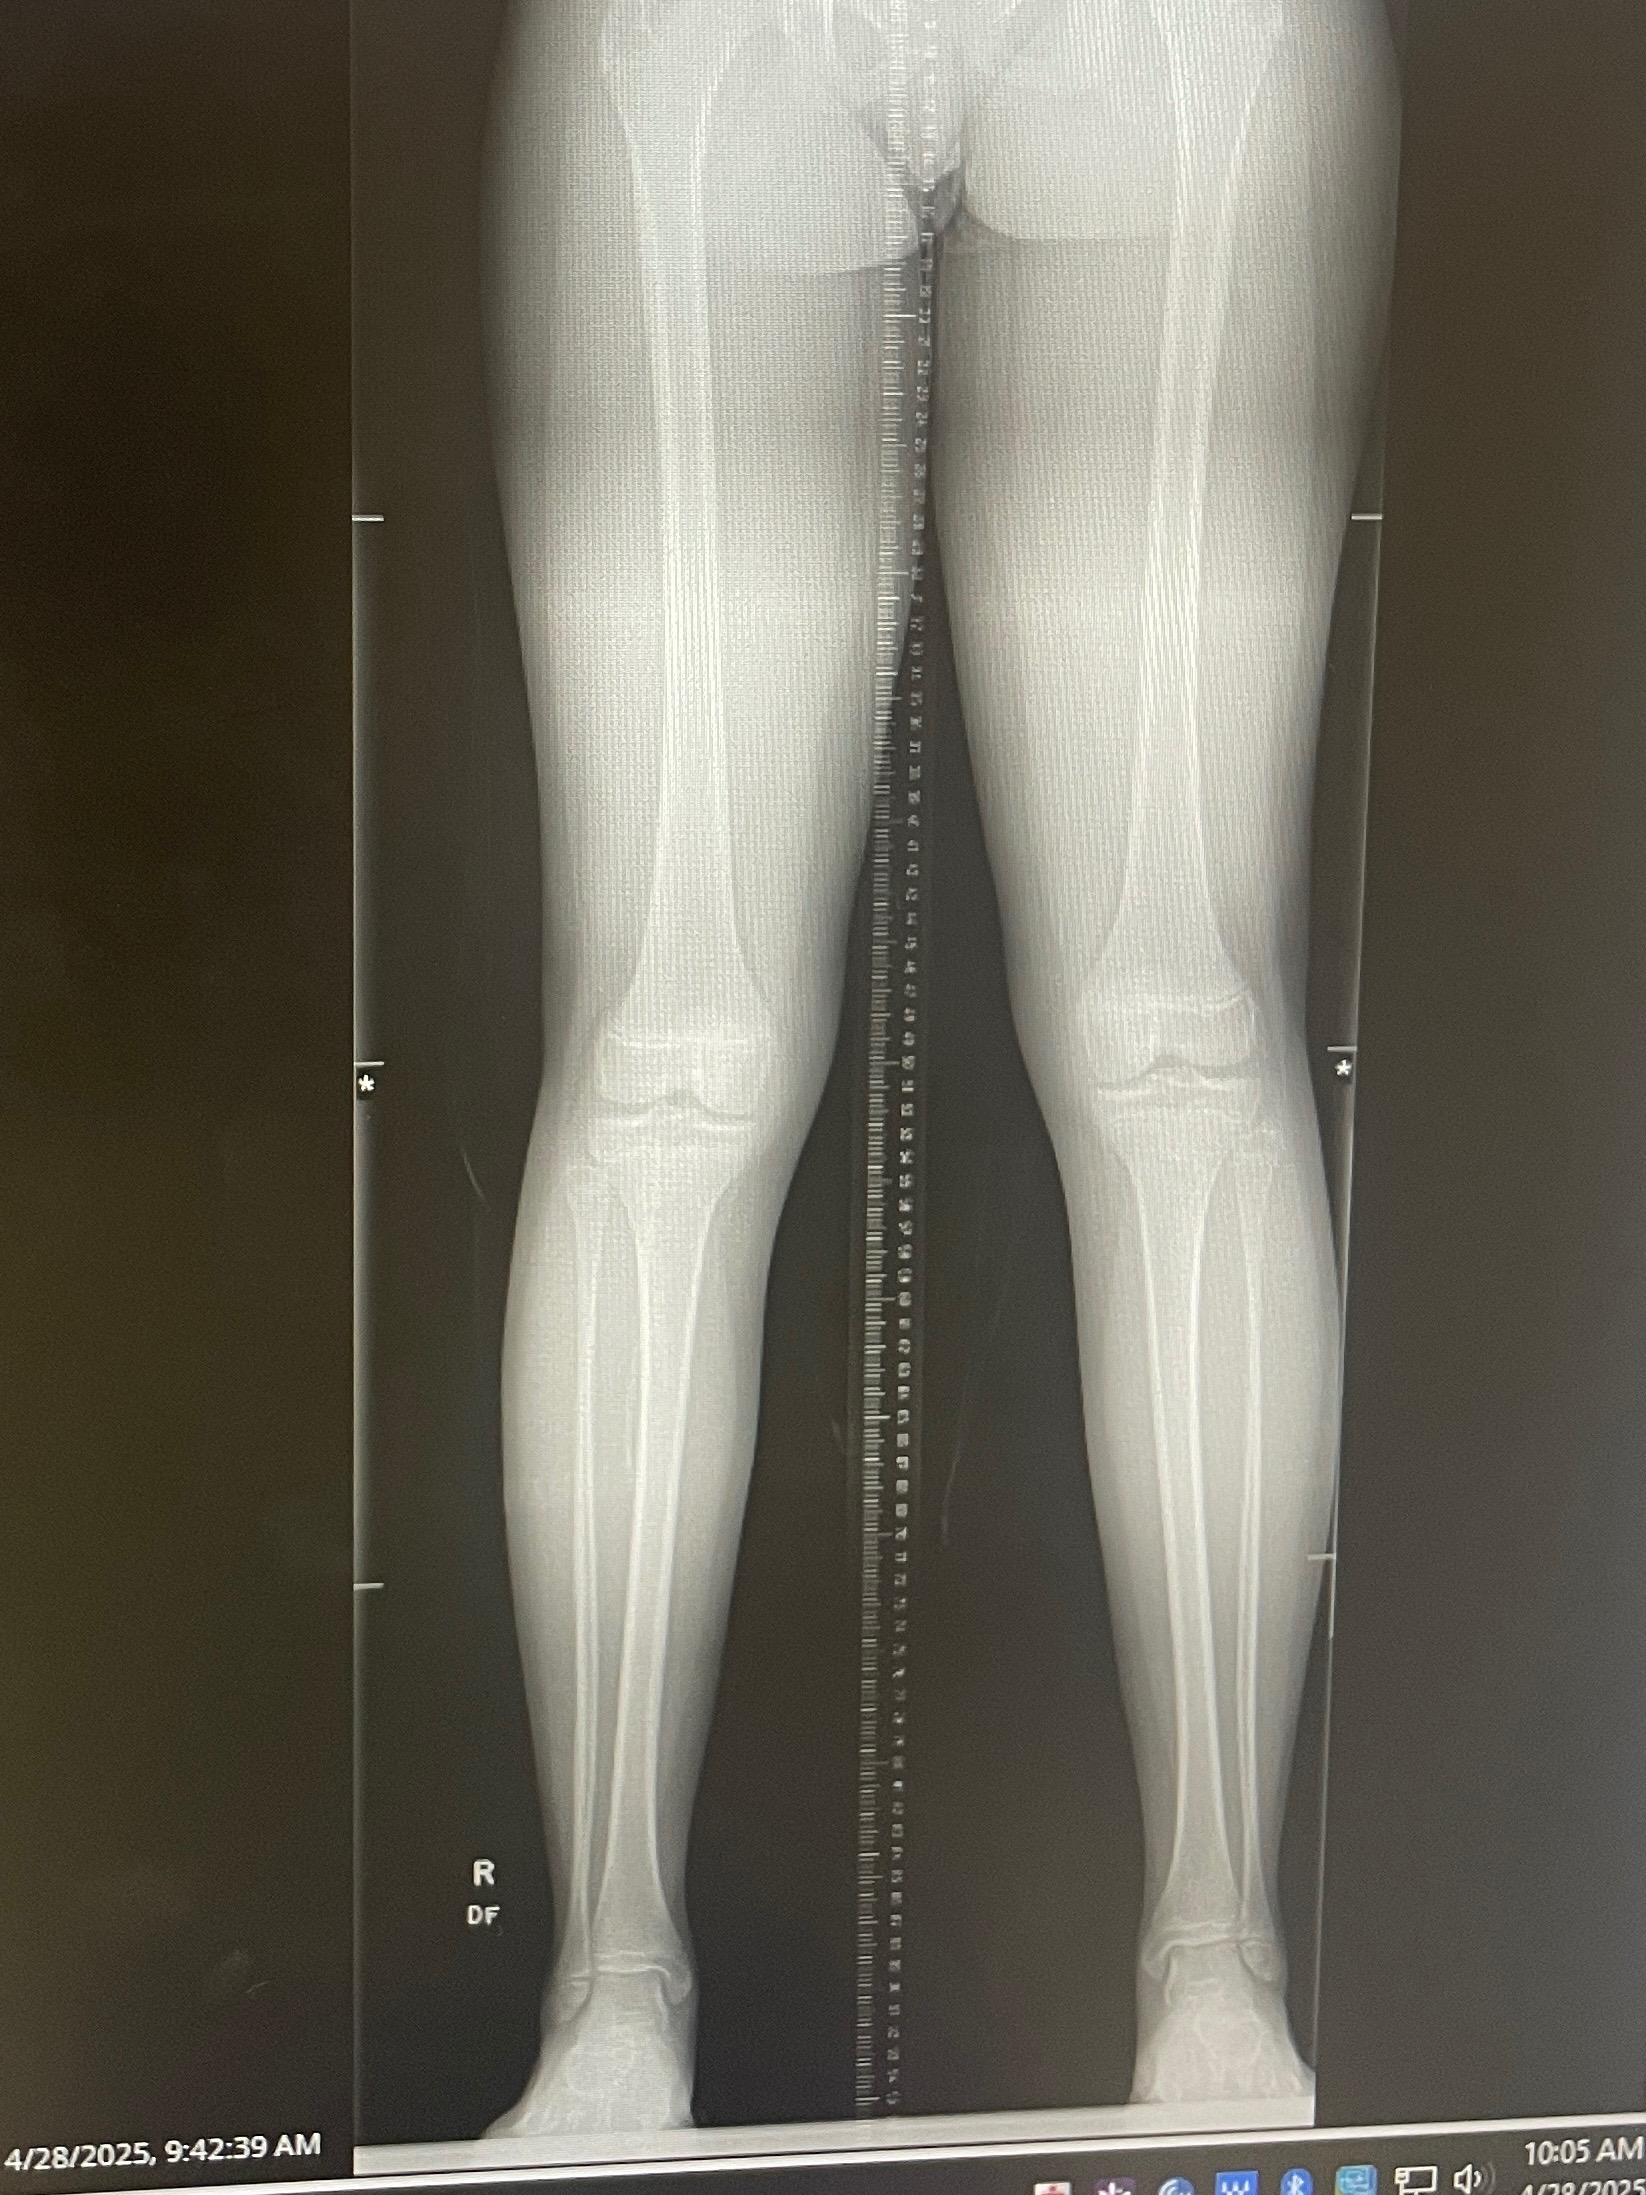

Amira is a passionate dancer, cheerleader, pageant competitor, and contortionist with scoliosis. Diagnosed at 9 years old, she was placed under a “wait and see” plan with her pediatric orthopedic team. Unfortunately, her condition has rapidly worsened and progressed to an S-shaped spinal curve measuring 38degrees. Additionally, she has a knee-length discrepancy caused by her scoliosis that is further complicating her condition.

To slow the progression and avoid an invasive and very costly spinal fusion surgery, Amira will need to wear a specialized brace until she’s done growing and undergo a noninvasive knee surgery. This treatment will preserve her ability to move freely and continue pursuing the activities she loves. However, our insurance does not cover the brace, even though it's considered medically necessary; the total cost we are responsible for is $5,000